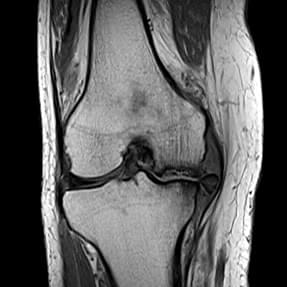

71歳/女性

右ひざのお悩みと診断

- 立ち上がるときに強く痛み、夜間痛もあり。

- ヒアルロン酸注射も効かず、人工関節を勧められたとのこと。

- 良い話を聞かないので手術したくないが、現状維持も嫌で再生医療を検討。

- MRI画像より、変形性ひざ関節症グレード4(末期)と診断。

大腿骨内側に突発性骨壊死があり、半月板も外周へ逸脱

膝蓋大腿関節に水がたまっているのが白く確認できる